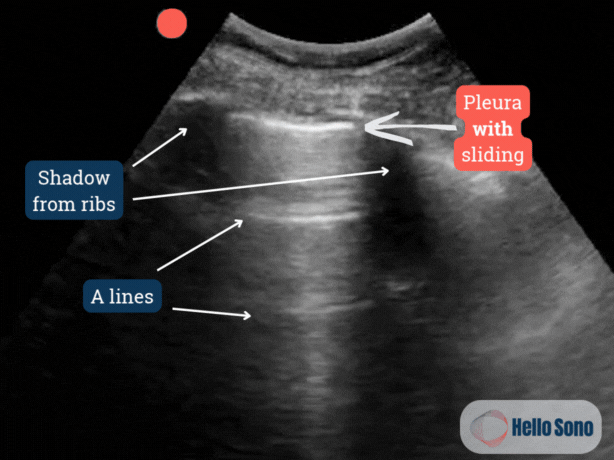

In a healthy individual, lung POCUS shows continuous pleural sliding, a shimmering horizontal motion of the visceral and parietal pleura during respiration (Clip 3).

annotated image of normal lung

Clip 3: Ultrasound clip of the normal lung showing pleural sliding with annotations.